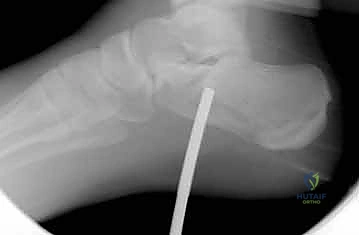

4. التثبيت المؤقت

يتم استخدام أسلاك معدنية دقيقة لتثبيت الشظايا في مكانها مؤقتاً، ثم يتم التحقق من دقة الرد باستخدام جهاز الأشعة السينية داخل غرفة العمليات (C-arm) لضمان عدم وجود أي انزياح ولو بمليمتر واحد.

صور إضافية من داخل غرفة العمليات توضح دقة الإجراء

توضح الصور التالية مدى تعقيد الجراحة والدقة التي يتطلبها تثبيت عظم الكعب، والتي يعكسها التميز الجراحي للأستاذ الدكتور محمد هطيف: